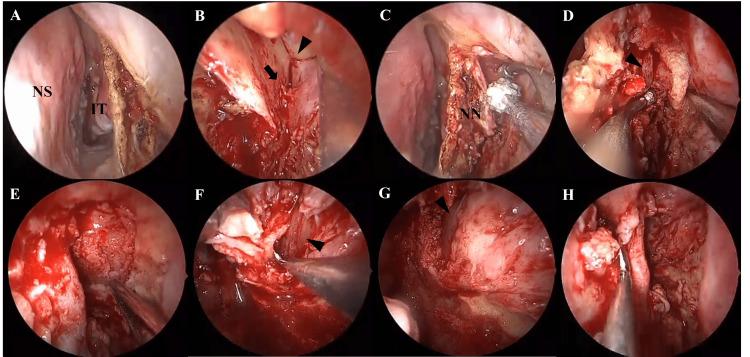

IgG4相关疾病(IgG4-RD)是一种慢性炎症性疾病,其特征为血清IgG4水平升高、IgG4阳性浆细胞浸润以及各器官纤维化。我们报告一例76岁男性患者,其表现为左侧眼球突出。计算机断层扫描显示左侧眼眶有一肿块病变。在局部麻醉下经鼻进行的初次活检结果不明确。尽管在全身麻醉下进行了内镜鼻窦手术,但仍无法获得明确诊断。病变持续增大,随后的眼科检查显示视神经受压逐渐加重。因此,再次在全身麻醉下采用内镜Denker入路进行肿瘤切除。肿瘤成功切除,无并发症发生。组织病理学检查结果提示可能为IgG4相关眼病(IgG4-ROD)。手术后,残留病变再次增大;然而,为期三天的类固醇脉冲疗法使病变缩小,视神经压迫症状改善。患者至今未复发。虽然81%的IgG4-ROD病例累及泪腺,但翼腭窝、三叉神经分支、眼外肌、眶脂肪、眼睑和鼻泪管等其他眼眶结构也可能受累。在不累及泪腺的病例中,应个体化考虑获取诊断性活检标本的最佳方法。尽管对于诊断所需的组织量尚无共识,但我们认为积极切除中央病变对于准确诊断是必要的。内镜Denker入路有助于广泛暴露和切除上颌窦外侧远部病变,既能实现减压又能进行明确诊断,从而为后续适当治疗提供依据。